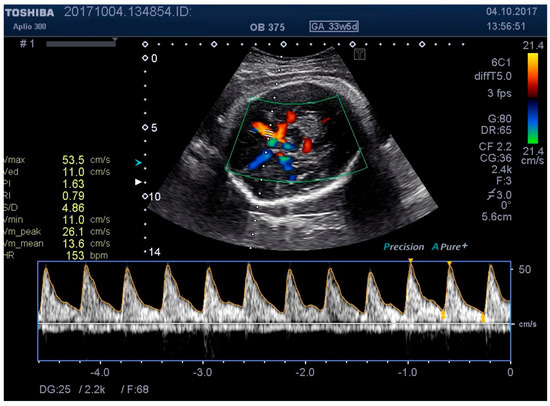

Figure 6. MCA Doppler spectrum with level 2 pressure.

Medicina 55 00410 g006

We examined the patients by transabdominal US, evaluating fetal lie and presentation, amniotic fluid index (AFI), area of placental insertion, and the abdominal wall thickness (AWT) including skin, subcutaneous tissue, and muscular wall. As a second step, we have evaluated the fetal cerebral vascularization, referring to the circle of Willis, with the help of color Doppler US, demonstrating the fetal MCA and recording the distance between the probe and the targeted vessel (e.g., MCA). By using pulsed Doppler examination, we recorded the flow velocity waveforms in the MCA, and measured the RI, PI, and PSV (using the highest point of the waveform). At the same time, we recorded, in a blinded manner, the applied pressure on to the maternal abdominal wall, considering this as a baseline pressure—needed for a proper evaluation of MCA. We then repeated the same measurements at two different higher pressure levels, while at the same time having a proper image of the targeted vessel. For the study methodology, we noted these pressure levels as level 2 and level 3.

Figure 1, Figure 2, Figure 3, Figure 4, Figure 5, Figure 6 and Figure 7 and Table 3 show the differences between MCA RI, PI, and PSV measured in the studied group, applying three different levels of abdominal pressure. As shown in the subsequent tables and figures, there are significant differences for the PI and RI levels with increase in abdominal pressure (median PI 1.46, 1.58, and 1.92, respectively; median RI 0.74, 0.78, and 0.85, respectively). Data are not following the normal distribution, thus, we used a Kruskal–Wallis test, which confirmed p < 0.05, for both PI and RI. At the same time, we found no significant differences for PSV in the studied group in relation to the increase in abdominal pressure (median PSV 39.56, 40.10, and 39.70 respectively). Data are not following the normal distribution, thus, we used a Kruskal–Wallis test, which showed p > 0.05.